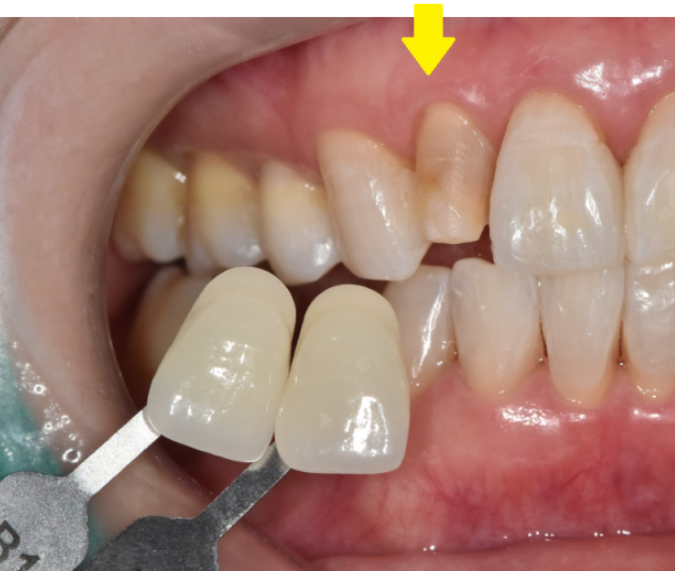

두번째, 치아 크기와 모양 배열

특정 치아가 크기가 작으면 효과적입니다.

그 치아만 크기를 키워주면 되니까요~

세번째, 치아 사이 약간의 간격

앞니가 벌어진 환자분들은 무삭제 라미네이트가 딱입니다!

공간이 너무 크지 않은 경우 간격을 메꿀 수 있거든요~

치아 색깔이 어두운 경우

연령 증가나 음식, 음료로 인한 약한 변색은

무삭제 라미네이트로 충분히 커버 가능합니다.